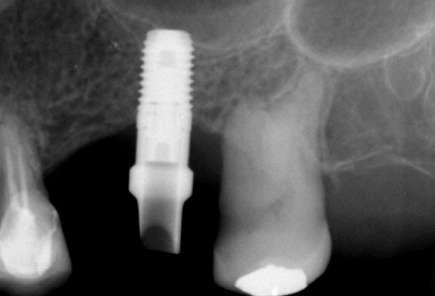

Figuras 3-6. Imágenes de un caso de prótesis atornillada en molar unitario inferior. Vemos el estado de los tejidos blandos gingivales tras la segunda fase y colocación del transepitelial unitario y la radiografía. En las imágenes inferiores (5 y 6) observamos el caso a los 4 años y 10 años de seguimiento, con estabilidad completa de los tejidos óseos peri-implantarios.

Figuras 7-10. En las dos imágenes superiores (7 y 8) observamos la realización de la prótesis cementada mediante un bioplilar fresado a la altura gingival con la radiografía antes del cementado de la corona. En las imágenes inferiores (9 y 10) vemos la prótesis a los 7 años de seguimiento y a los 9 años transformada en una prótesis atornillada al perderse la pieza anterior al implante y realizarse un puente con el nuevo implante. En este caso, el nivel óseo permanece estable con el paso del tiempo.